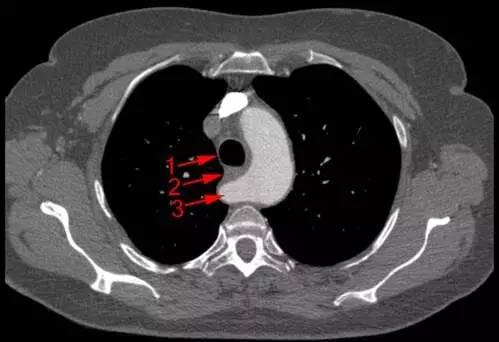

「迷路」的右锁骨下动脉—迷走右锁骨下动脉

锁骨下动脉,为啥迷路了?